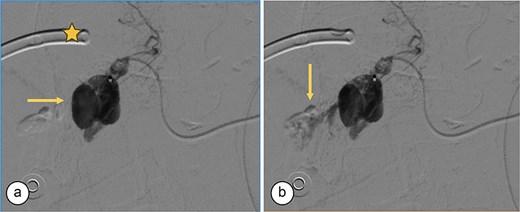

Surgical reconstruction revealed an excluded PRHD and ARHD–LHD continuity with obstruction 10 mm from the confluence. The PRHD catheter was found outside the biliary tract, so a transhepatic Nelaton catheter was placed from inside to out. A neoconfluence of PRHD with ARHD and LHD was created with a 30 mm hepaticojejunostomy. A transanastomotic Nelaton catheter and a supranastomotic ARHD catheter were left in place. Estimated blood loss: 300 cc. In the immediate postoperative period, the patient developed melena and bleeding from the Penrose drain. Cholangiography via the right percutaneous catheter showed no contrast leakage. Angio-CT revealed an 8 × 5 mm saccular lesion in the anterior right hepatic artery (Segment V), consistent with a pseudoaneurysm (Figs 1 and 2). Selective embolization with three microcoils (2 × 3 × 2.3 mm) was successfully performed (Fig. 3). The patient had a favorable recovery, with no further bleeding, and was discharged in stable condition for outpatient follow-up. Control imaging of the ARHD catheter confirmed adequate visualization of all hepatic ducts, allowing catheter removal (Fig. 4).

Transcatheter arterial embolization of the right hepatic artery. (a) Selective transcatheter arterial embolization (TAE) of the branch of the right hepatic artery (Segment V) (arrow). (b) Post-embolization image of the pseudoaneurysm in the branch (Segment V) of the right hepatic artery with microcoils (arrow), showing no contrast medium leakage. Right percutaneous catheter (star).